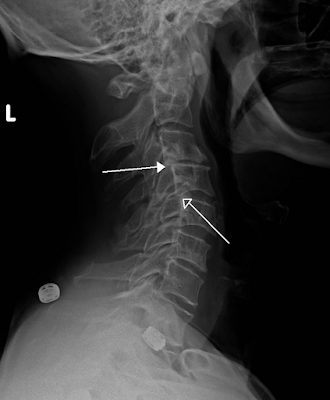

- Artrosis espinal o facetaria. Es la degeneración de las articulaciones facetarias de la columna vertebral. Se encuentran en la parte posterior de las vértebras, y ayudan a proporcionar estabilidad y movimiento a la columna. Figura 2

Figura 2. Artrosis facetaria. Rx lateral de columna. Afectación de articulaciones facetarias (flechas)Fuente: ver aquí